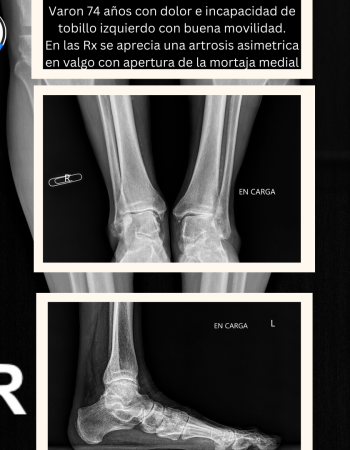

En la radiografías en carga se aprecia una artrosis asimétrica con el tobillo en valgo, muy probablemente debido a una inestabilidad medial por lesión del ligamento deltoideo.